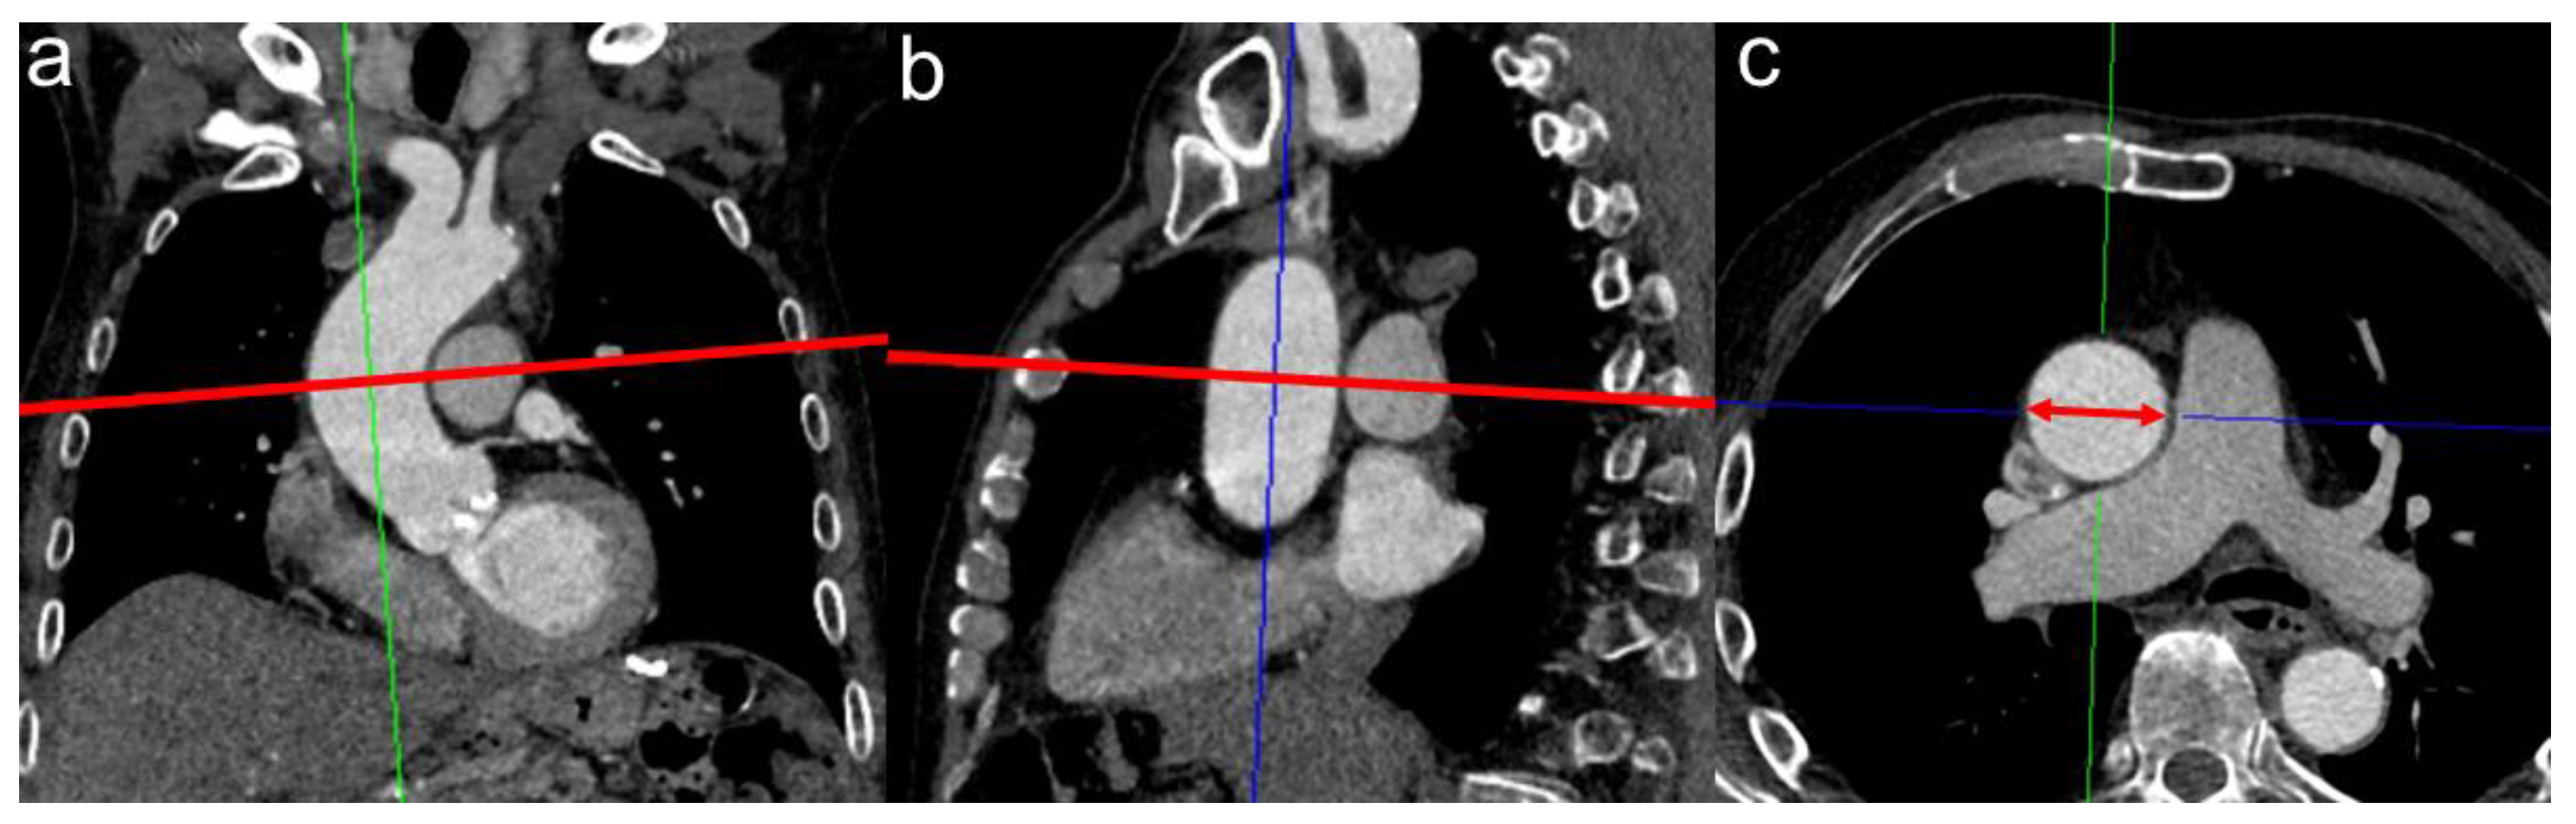

An illustration of the radiological measurement of the AA is shown in Figure 2.

Figure 2.

Measurement of the tubular ascending aorta at the level of the pulmonal artery bifurcation. Corrected axial vessel diameter was established using the multiplanar reconstruction plug-in of Deep Unity Diagnostics. The ascending aorta was manually corrected perpendicular to its centerline in coronal (a) and sagittal reconstruction (b). The obtained corrected axial aortic cross-section was measured (red double-headed arrow in (c)), and the widest diameter was used as maximum diameter.